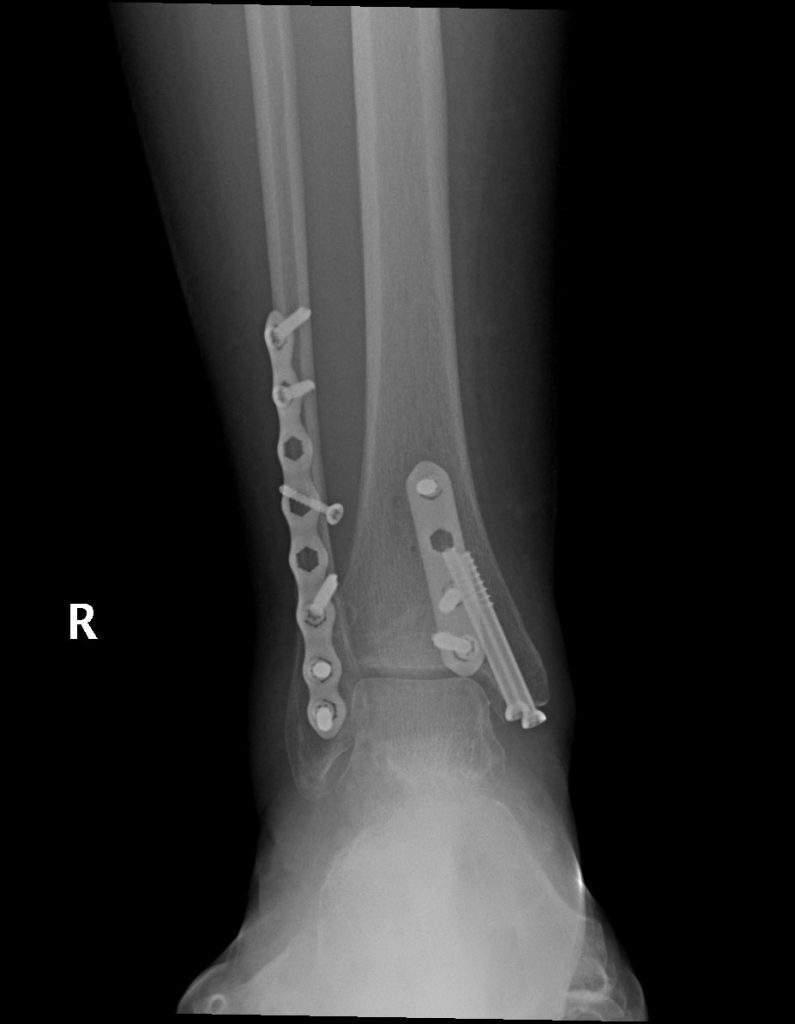

Having never broken anything before, I have always lived in fear of it. I had a very bad fall and fractured all the bones in my ankle this summer. Thankfully, the ambulance was willing to take me to HSS at NYP. The doctors in the ER were great and did the best they could, but it was obvious I would need surgery. Dr. Stephen Behrens, his PA Meagan Murtagh, and the entire staff are amazing and work miracles. My surgery was scheduled immediately and went off smoothly. It has taken a lot of effort and physical therapy in the past few months to get Back in the Game, but I owe a lot to this team. There's a reason that this hospital is number one in the country for orthopedic surgery and Dr. Behrens certainly lives up to the reputation.